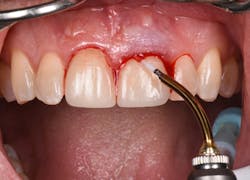

Figure 12: Pre-op clinical photo shows the discrepancies and disharmony of the gingival height. Incisions for esthetic crown lengthening on tooth No. 9 were done via the Er:YAG laser in contact mode (20 pps/60 mJ) to remove excess soft tissue in accordance with the pre-op probing depth measurements.

Figure 13: Exposure of the bony tissues via a full-thickness flap shows osseous irregularities and exostosis ledges that are contributing to the gingival discrepancy. Calculus can be observed attached to the root surface of the teeth.

Figure 14: After osseous shaping and recontouring was done using the Er:YAG laser in contact mode (20 pps/80 mJ). All bony ledges and crestal bone were removed on teeth Nos. 9–11.

Figure 15: Immediate post-op of tissues repositioned into place. Simple interrupted sutures were used.